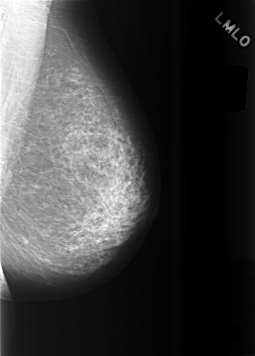

C_0474_1.LEFT_MLO

LEFT_MLO LINES 5696 PIXELS_PER_LINE 4080 BITS_PER_PIXEL 12 RESOLUTION 50 NON_OVERLAY